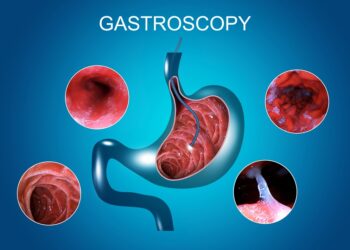

Stemplė – tai raumeninis vamzdelis, kuris atsakingas už maisto, gėrimų ir seilių judėjimą iš burnos į skrandį. Stovint suaugusio žmogaus...